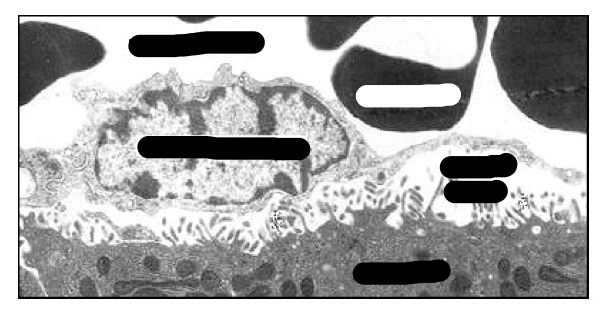

What are the different cells shown on this image of a sinusoid?

What are the following labels?

What are the following missing labels?